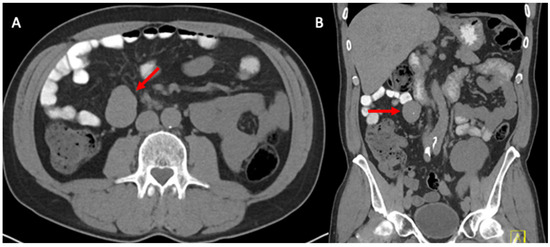

2. Case Report